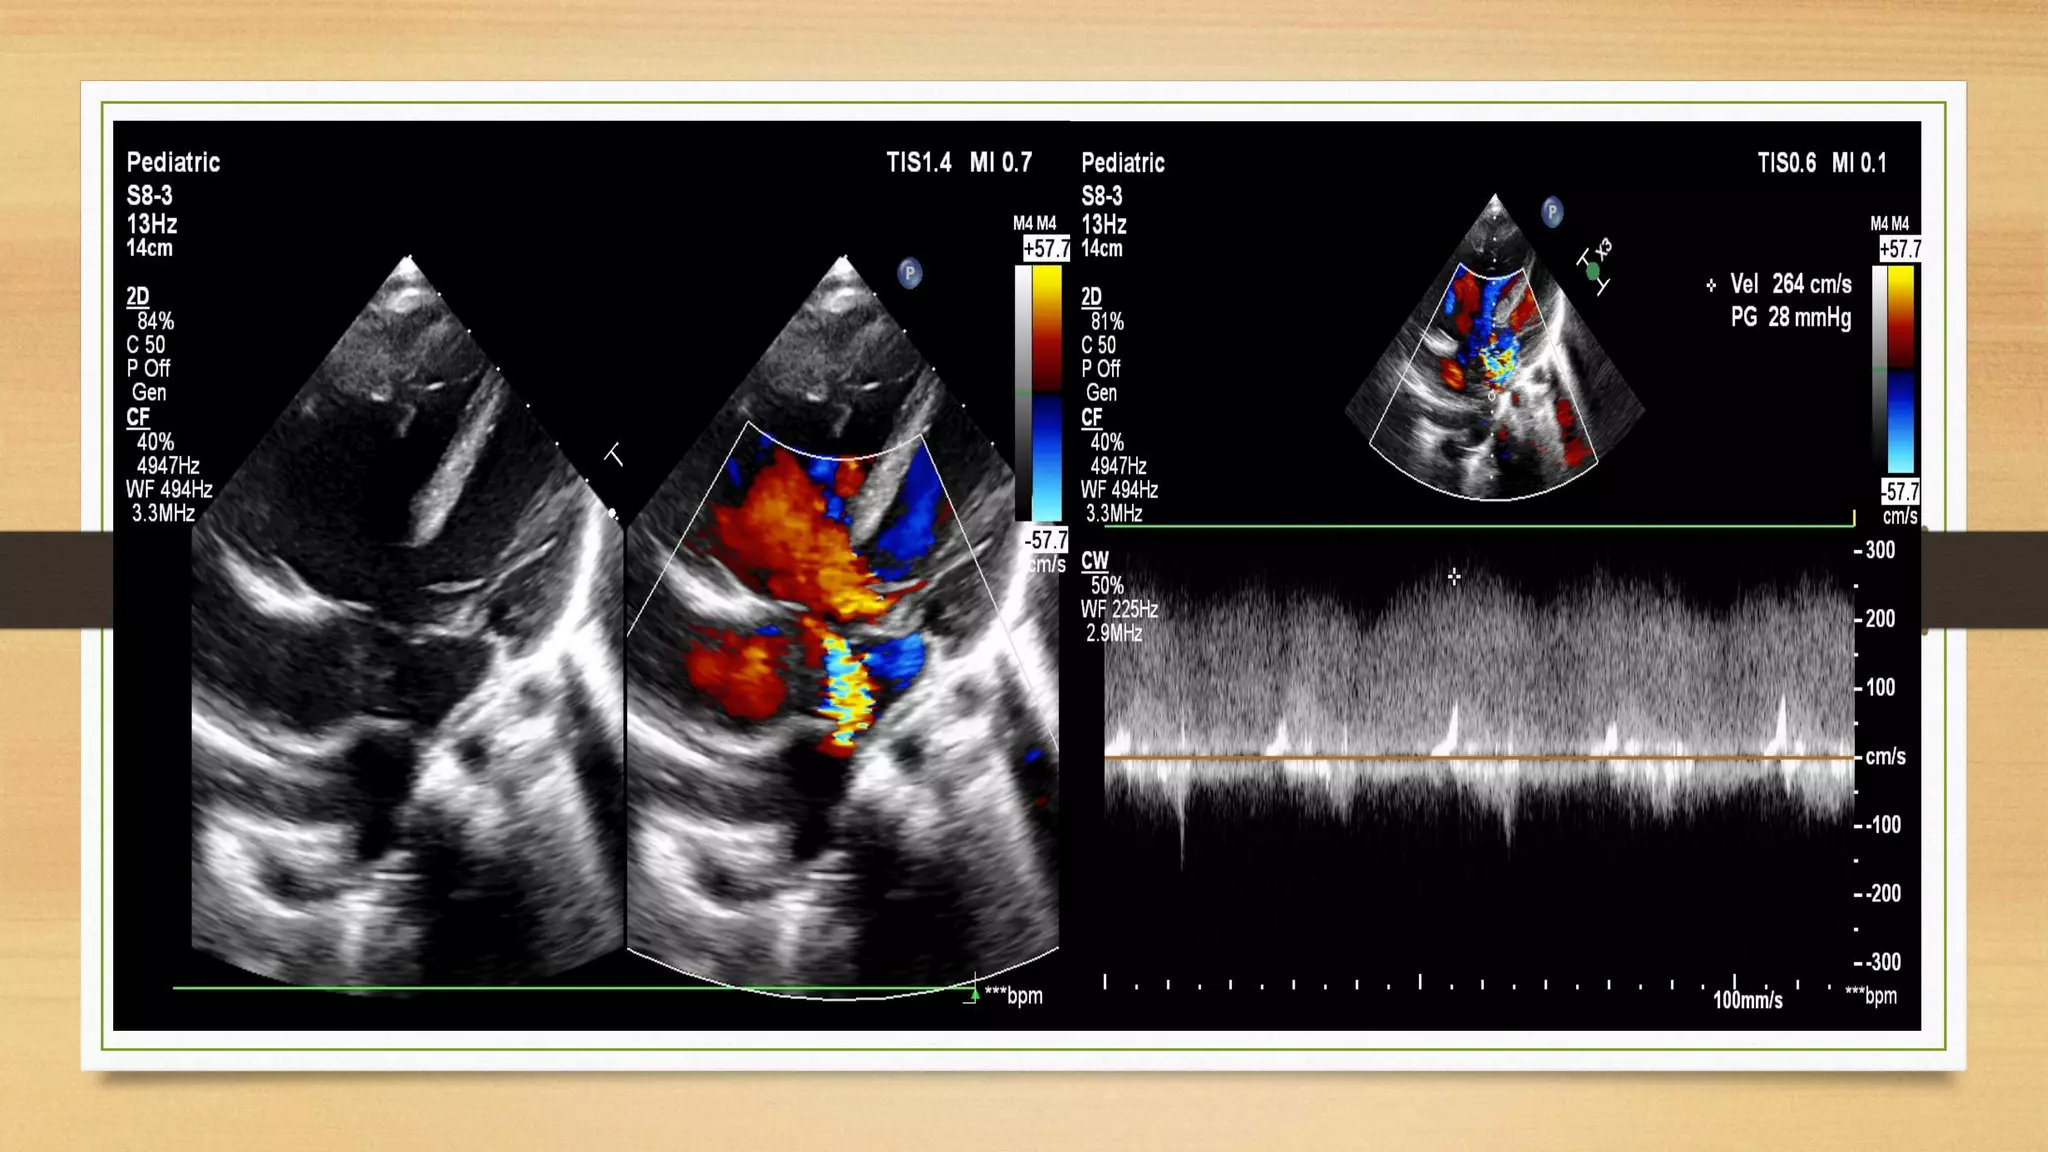

Balanced Complete A V S D

balanced AVSD Complete E D with TAPVC